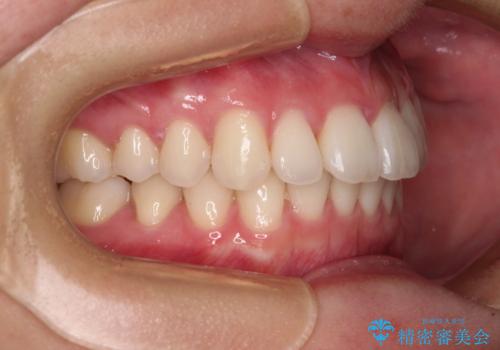

【モニター】犬歯のクロスバイトを目立たないワイヤー装置で

- 20代女性

- 矯正装置

- クリアブラケット

- 治療期間

- 1年6ヶ月

思っていたよりも早くクロスバイトは改善され、歯髄壊死に至ることなく、無事に治療を終えることができました。